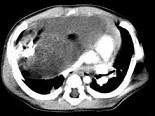

问题 男,28岁,胸闷、右肺呼吸音减弱,请结合影像图像,选择最可能的诊断 ( )

选项 A.畸胎瘤 B.胸腺瘤 C.肺癌 D.先天性囊性腺瘤样畸形 E.支气管囊肿

答案 A